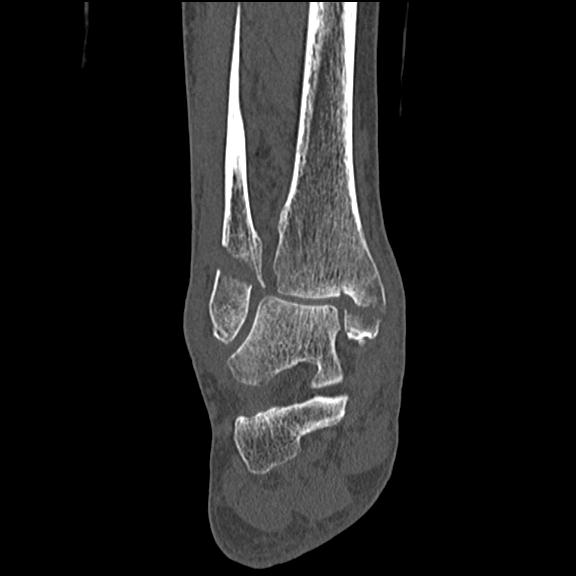

56476 8/28 4R 1/21 2R 左足関節 デジカメ写真 72歳女性 右足関節AS

102755 1/4 2R 1/15 2R 右足関節 68歳女性 右三果脱臼骨折

103177 3/11 右足 2R 3/16 右足 2R リスフラン脱臼 55歳男性